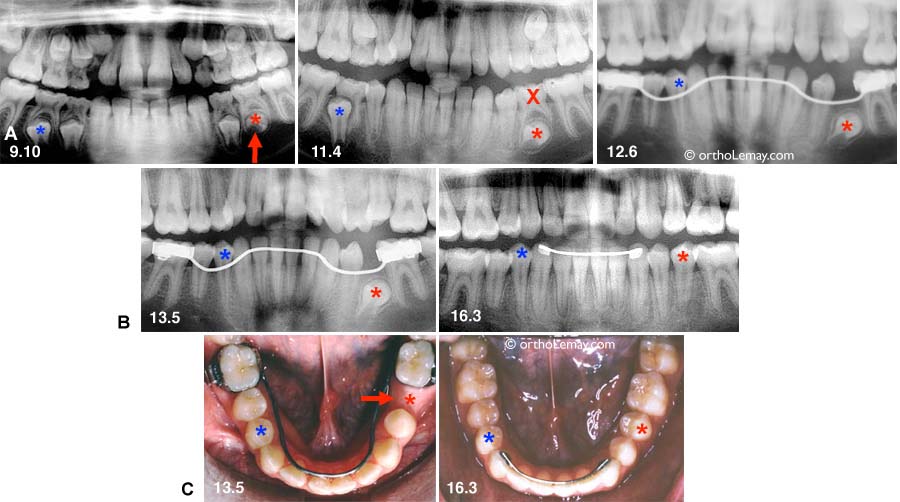

Supervision inadéquate à l’arcade inférieure.

(A) La migration vers l’avant des molaires créé une perte d’espace qui empêche l’éruption des deuxièmes prémolaires inférieures. L’utilisation d’un mainteneur d’espace aurait pu prévenir ce problème ou le minimiser.

(B) Les corrections orthodontiques ont replacé les dents où elles auraient dû être maintenues par un mainteneur pendant leur éruption.